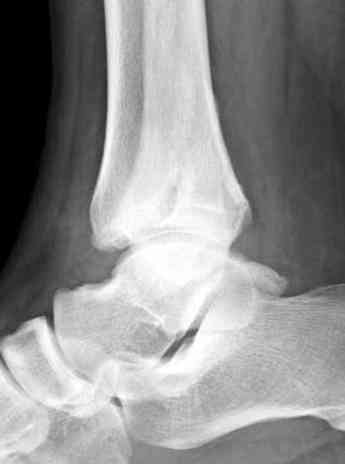

Мне кажется есть все основания попытаться сделать остеосинтез. Боль вследствие нестабильности. Нестабильность вследствие неанатомичного положения дистального отломка малоберцовой кости. Через 1,5 вполне возможно разобщить, репонировать и фиксировать длинный косой перелом наружной лодыжки. Вероятно, одновременно придется делать медиальный доступ для мобилизации внутренней лодыжки. Мы оперируем таких пациентов, функциональные (объем движений) результаты конечно хуже по сравнению с теми кого оперируем в первые 5-10 дней, но вполне удовлетворительные.

Согласен, на предоставленных рентгенограммах все основания для проведения открытого остеосинтеза.

сроки действительно небольшие, но если мы его и возьмем, то пройдет еще минимум неделя, кроме того смущает впечатление сращения н/лодыжки, похоже, что придется не разобщать,а остеотомировать, формирование оссификатов в полости сустава с медиальной стороны, да и сам пациент 1,5 месяца по поводу своей травмы сильно не напрягался